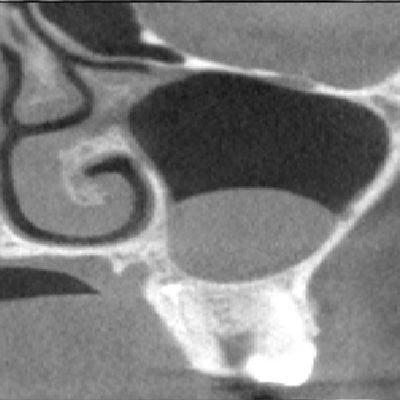

Additionally, the man's upper left second premolar was missing. A panoramic x-ray revealed bilateral kissing molars in his lower quadrants linked with cystic lesions encompassing the molar crowns. Also, it was noted that an ectopic upper right #8 tooth accompanied an associated mass in the right maxillary antrum. To determine the risks of surgically removing these teeth, the man was told to get a CBCT scan, the authors of the case report wrote.

- A 17 mm vertical x 18 mm mediolateral x 24 mm anterior-posterior corticated soft-tissue mass in the right maxillary sinus, which was intimately involved with the displaced upper right tooth #8

- Thinning of the right maxillary sinus wall with a vertical dimension in excess of 28 mm and a mass involving the crowns of the upper right teeth #8 and #7

- The apices of the upper right tooth #8 were dilacerated and engaged the lateral wall of the right maxillary sinus

- The roots of the upper right tooth #7 engaged the floor of the maxillary sinus and the floor of the right nasal cavity, and the tooth's root was situated between the roots of the upper right #6 tooth

In some cases, there is a high risk of pathological fracture and inferior alveolar nerve injury. Deflection of the roots, narrowing of the roots, diversion of the canal, and narrowing of the canal are features found on imaging that would suggest a high risk of inferior alveolar nerve damage. In such cases, a CBCT scan can provide beneficial information about the buccolingual positioning of the inferior alveolar nerve and the width of the remaining bone, which aids in treatment planning, the authors wrote.